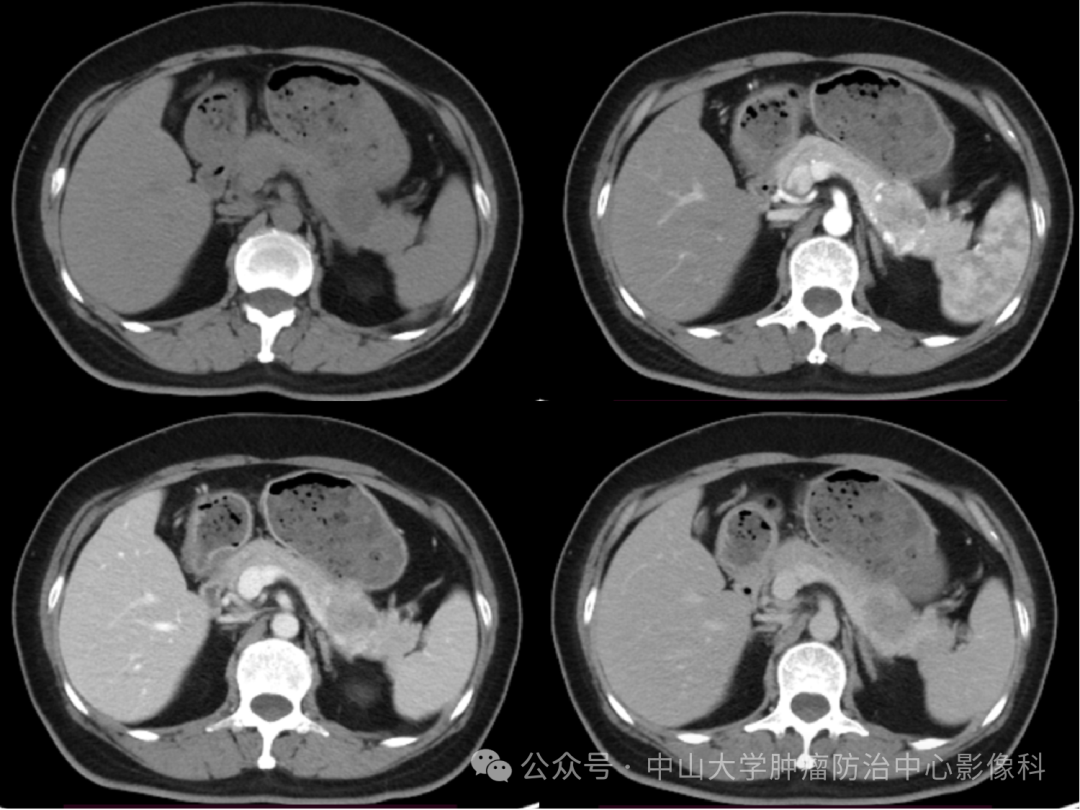

胰腺浆液性囊腺瘤是一种起源于胰腺的良性囊性肿瘤其核心特征与诊疗要点如下病理特征该肿瘤由胰腺腺泡或导管上皮细胞形成,囊壁由单层扁平或立方上皮覆盖,囊液通常为清亮或淡黄色影像学检查如CTMRI显示其典型表现为边界清晰的囊性占位,内部可见多个小囊腔,形成“蜂窝状”或“葡萄串样”。